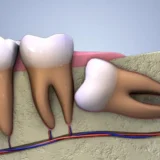

Chụp X quang răng là một trong những kỹ thuật quan trọng, giúp ghi lại toàn bộ hình ảnh trong khoang miệng. Từ hình ảnh này, nha